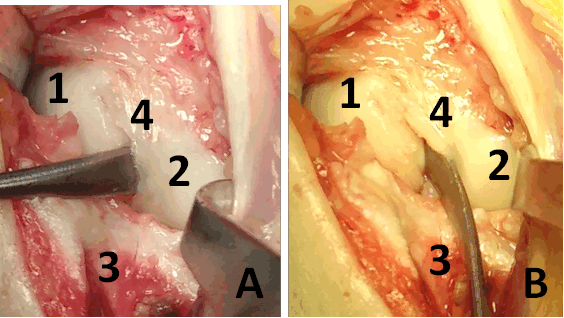

Описание техники оперативного лечения. Операция проводилась под региональным обескровливанием при помощи пневматического жгута. В положении пациентки на спине рука располагалась на приставном столике. Выполнялся тыльный продольный доступ в проекции лучезапястного сустава. Остро и тупо препарировались мягкие ткани с визуализацией сухожилий разгибателей пальцев кисти. Удерживатель сухожилий разгибателей рассекался в третьем компартменте, после чего сухожилия разгибателей пальцев кисти разводились в разные стороны. Капсула сустава рассекалась Т-образно. В полости лучезапястного сустава визуализировалось избыточное содержание синовиальной жидкости, разрастание синовиальной оболочки сустава, отрыв ладьевидно-полулунной связки (рис. 3). При ревизии трехгранного комплекса патологических изменений выявлено не было. Осуществлялось проведение биодеградируемого пина 1,5 мм через ладьевидно-полулунное сочленение по оси полулунной кости для сопоставления костей проксимального ряда запястья. Контроль положения ладьевидной и полулунной костей был исследован при помощи электронно-оптического преобразователя (далее ЭОП). В область дефекта ладьевидно –полулунной связки в проксимальный полюс ладьевидной кости устанавливался биодеградируемый якорный фиксатор с последующим восстановлением целостности поврежденной тыльной порции ладьевидно-полулунной связки (рис. 4). Восстановление осуществлялось за счет формирования дубликатуры культи связки и её трансоссальной фиксации к полулунной кости. В дальнейшем осуществлялась пластика капсулы лучезапястного сустава. Восстанавливалось положение сухожилий разгибателей пальцев правой кисти, осуществлялась пластика удерживателя сухожилий.

Рис. 3. Фотография операционной раны. А, B: 1 – ладьевидная кость, 2 – полулунная кость, 3 – лучевая кость, 4 – полулунно-ладьевидная связка.

Между ладьевидной и полулунной костями в дефект установлен элеватор